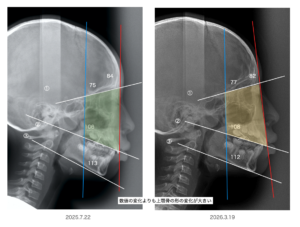

ではこのお子さんの変化を見てみましょう!

この緑と黄色の部分が「上顎骨」です

いかがですか?これは半年の変化です

四角形のしたの方が長く伸びていますよね。。。

これは呼吸が良くなってきたことを意味します